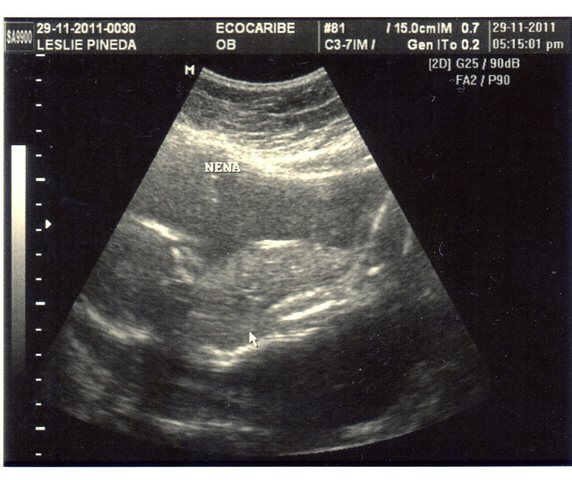

• 5° Ecografía. ES UNA NENA !!!!!!

5° Ecografía. ES UNA NENA !!!!!!

Ecografía número 5: Y te volvemos a ver, estas grandota y la Dra nos dice,"Es una nena". Tú mamita quedó muda por un rato largo! Tú papí FELIZ!!!!!